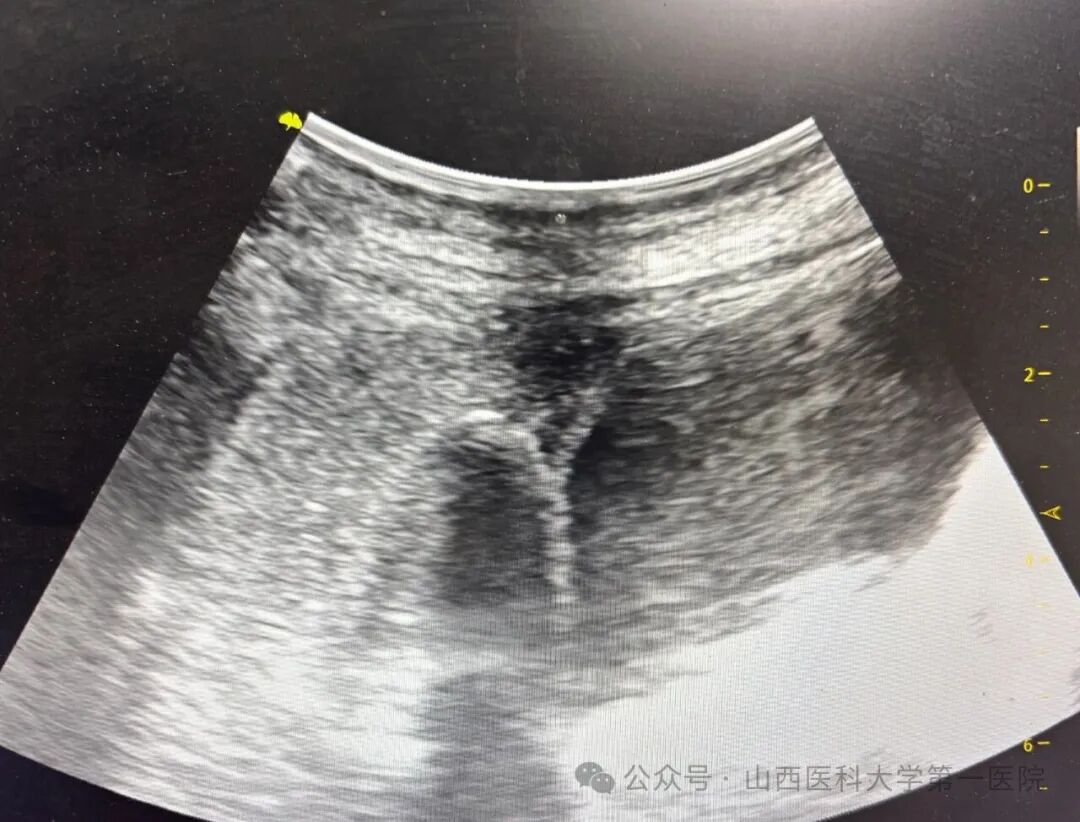

患者入院后,肿瘤综合科经过疑难病例微创术前讨论一致认为,该患者化疗联合免疫治疗失败,如及时实施局部消融治疗,能够带来生存和生活质量双获益,但是肿瘤所在位置为胆囊窝,解剖结构十分复杂,如果实施常规热消融,则术中90-300°C的热量弥散会导致局麻患者术中剧烈疼痛难以忍受,且术后胆瘘发生率极高,根据目前经皮冷冻消融治疗中国专家共识相关推荐条款,完成知情同意流程后,遂决定采取-150°C超声引导局部麻醉下胆囊窝肿物冷冻消融治疗术。手术全程患者无明显疼痛及腹胀加重,意识清醒,可随时与操作医生保持良好沟通,经过两次-150°C冷冻循环,60min操作过程,手术顺利完成。

肿瘤冷冻消融是一种经皮肿瘤微创治疗技术,通过影像引导(如超声、CT、MRI、PETCT)将冷冻消融电极经皮穿刺入肿瘤病灶,利用液氮、氩气等冷媒产生的极低温(-150℃至-40℃)破坏肿瘤细胞及滋养血管,导致肿瘤病灶毁损,适用于泛瘤种,有微创、保脏器、恢复快、可重复等诸多优势。